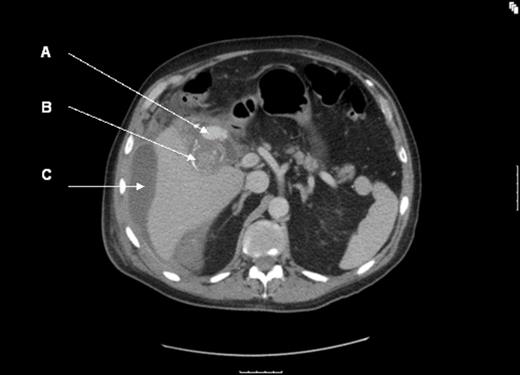

His condition remained stable; however, over the course of the next 7 days, he began spiking temperatures along with persistent RUQ pain and increasing leucocyte count. An abdominal USS was repeated which now demonstrated a single large calcified gallstone within a contracted gallbladder and a pulsatile mass around Hartman’s pouch with a large amount of free fluid around the liver. This fluid was extending into the right paracolic gutter and down to the right iliac fossa. A CT angiogram (Fig.1a & 1b) was done to delineate this pulsatile mass which confirmed a 3cm x 1.5cm cystic artery pseudoaneurysm (A) and a large collection (C) extending from the gall bladder fossa, surrounding the liver and extending down to the right paracolic gutter and into the pelvic brim. There was no suspicion of gallbladder perforation or empyema from the images obtained.

CT angiogram (A = cystic artery pseudoaneurysm; B = calcified gallstone; C = perihepatic fluid)